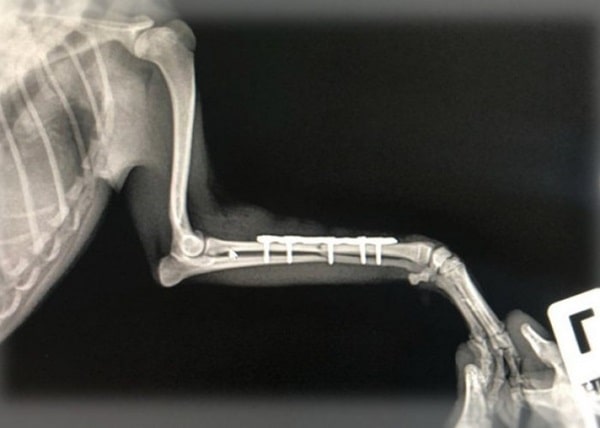

Лап

Переломи стегнових кісток у собак вимагають хірургічного лікування набагато частіше, винятків не так багато. Завданням хірурга в цьому випадку є максимально раннє відновлення опори на пошкоджену кінцівку. Для досягнення цієї мети необхідна функціональна репозиція кісткових уламків і їхня фіксація, що дає змогу передавати навантаження з дистальної частини кінцівки на проксимальну, минаючи ділянку перелому. При цьому спосіб стабілізації має враховувати характер ушкодження, анатомічну ділянку, і не повинен порушувати кровопостачання пошкодженої ділянки. У багатьох випадках, варіанти стабілізації конкретного місця травми можуть бути різними, якщо вони відповідають описаним критеріям.

Важливо пам’ятати, що хоча остеосинтез у ділянці кінцівок не є екстреною операцією, час дорогий. Оптимальними термінами для остеосинтезу є 1-3 дні після отримання травми, бажано, одразу після того, як пацієнта визнано стабільним і готовим до оперативного втручання.

Якщо з якихось причин операція відкладається, виникає низка додаткових проблем. Спазм м’язів спричиняє зміщення кісткових уламків назустріч один одному, що через деякий час вкрай складно подолати на операції, щоб забезпечити їхню правильну репозицію. Якщо ж час від ушкодження до операції ще триваліший (понад тиждень), можуть приєднуватися і додаткові негативні чинники. На цих термінах починають відзначати активний розвиток сполучної тканини, що додатково ускладнює хірургічне втручання. М’язи в ділянці перелому починають вкорочуватися, що призводить до контрактур. Крім цього, не маючи нормального навантаження, м’язи кінцівки починають атрофуватися, що вкрай ускладнює післяопераційну реабілітацію.